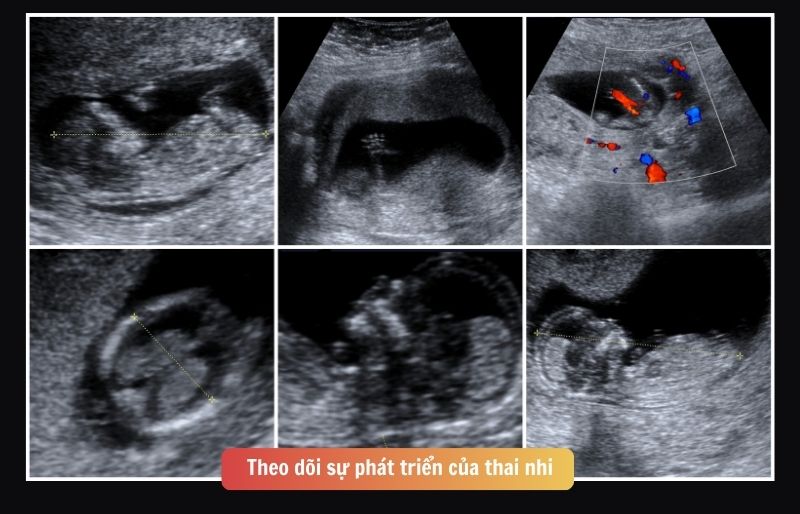

Theo dõi sự phát triển của thai nhi

Trong suốt thai kỳ, bác sĩ sẽ giúp mẹ theo dõi thai nhi để đảm bảo bé phát triển bình thường:

- Nghe nhịp tim thai từ tuần 10 – 12.

- Đo bụng để theo dõi sự tăng trưởng thai nhi từ tuần 20.

- Kiểm tra vị trí thai nhi, cử động.